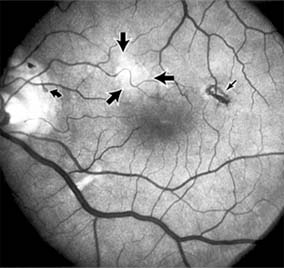

Central serous chorioretinopathy is characterized by serous detachment of the sensory retina as a consequence of focal leakage of fluid from the choriocapillaris through a defect in the retinal pigment epithelium (Figures 10-2 and 10-3). This disease typically affects young to middle-aged men and may be related to life stress events. Most patients present with the sudden onset of blurred vision, micropsia, metamorphopsia, and central scotoma. Visual acuity is often only moderately decreased and may be improved to near-normal with a small hyperopic correction.

Figure 10-2

Figure 10-2: Central serous chorioretinopathy with sensory retinal detachment (arrows) extending into the fovea.

Figure 10-3

Figure 10-3: Fluorescein angiogram of central serous chorioretinopathy shows active disease with both a retinal pigment epithelial detachment (small arrows) and a sensory retinal detachment (large arrows). Two foci of inactive disease (open arrows) are also present.

The diagnosis is made by slitlamp examination of the fundus; the presence of serous detachment of the sensory retina in the absence of ocular inflammation, subretinal neovascularization, an optic pit, or a choroidal tumor is diagnostic. The retinal pigment epithelial lesion appears as a small, round or oval, yellowish-gray spot that is variable in size and may be difficult to detect without the aid of fluorescein angiography. Fluorescein dye leaking from the choriocapillaris may accumulate below the pigment epithelium or sensory retina, resulting in a variety of patterns including the well-recognized smokestack configuration.